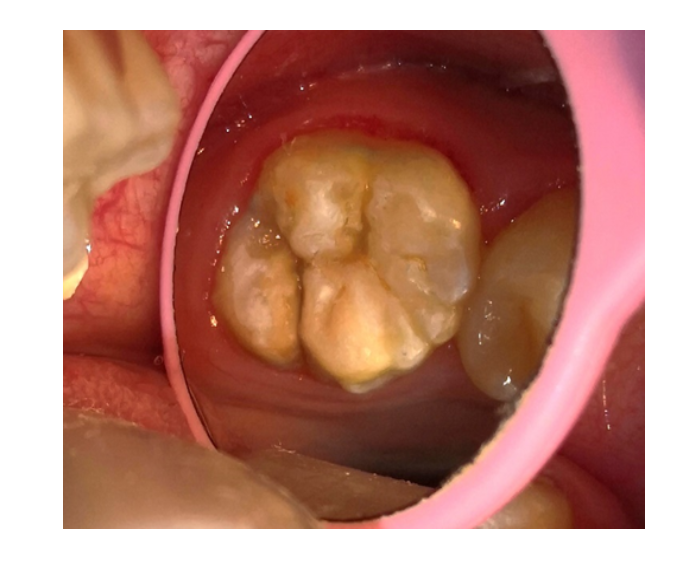

Selladores

/Resinas